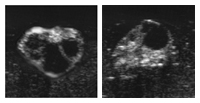

In der Brunst erreicht das Eibläschen (Follikel) in kurzer Zeit seine maximale Grösse. Sein Durchmesser erreicht 1.5 bis 2 cm Im Eibläschen befindet sich Flüssigkeit, die die Eizelle umgibt. Es ist gut möglich, dass der Gelbkörper (Corpus luteum) vom letzten Zyklus noch vorhanden ist. Er kann sich auf demselben Eierstock wie das Eibläschen oder auf dem anderen Eierstock befinden.

Ausnahmsweise können auch 2 Eibläschen gleichzeitig heranreifen. Auch dies kann auf demselben oder je auf einem Eierstock stattfinden. Daraus entstehen2-eiige Zwillinge. Eineiige Zwillinge gibt es, wenn sich die befruchtete Eizelle in einem frühen Entwicklungsstadium teilt.